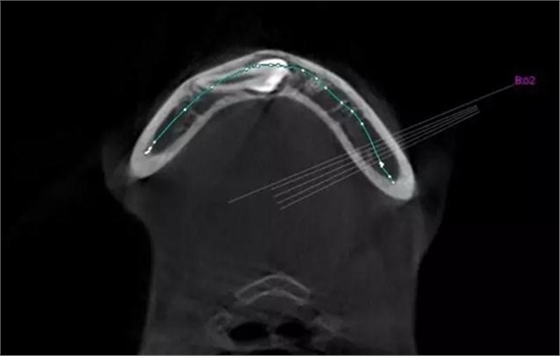

本案:患兒,女,14歲,因牙齒矯正來院,檢查見83滯留,43未見萌出,拍片發(fā)現(xiàn):43埋伏阻生于31、41、42根尖下方,按照正畸診療計劃,擬行43拔除術。

CBCT顯示